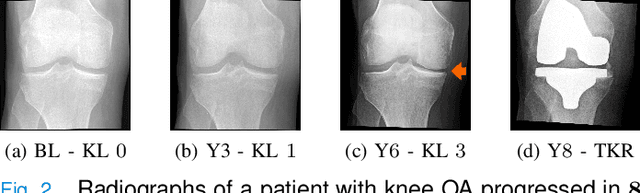

Abstract:Knee Osteoarthritis (KOA) is a highly prevalent chronic musculoskeletal condition with no currently available treatment. The manifestation of KOA is heterogeneous and prediction of its progression is challenging. Current literature suggests that the use of multi-modal data and advanced modeling methods, such as the ones based on Deep Learning, has promise in tackling this challenge. To date, however, the evidence on the efficacy of this approach is limited. In this study, we leveraged recent advances in Deep Learning and, using a Transformer approach, developed a unified framework for the multi-modal fusion of knee imaging data. Subsequently, we analyzed its performance across a range of scenarios by investigating multiple progression horizons -- from short-term to long-term. We report our findings using a large cohort (n=2421-3967) derived from the Osteoarthritis Initiative dataset. We show that structural knee MRI allows identifying radiographic KOA progressors on par with multi-modal fusion approaches, achieving an area under the ROC curve (ROC AUC) of 0.70-0.76 and Average Precision (AP) of 0.15-0.54 in 2-8 year horizons. Progression within 1 year was better predicted with a multi-modal method using X-ray, structural, and compositional MR images -- ROC AUC of 0.76(0.04), AP of 0.13(0.04) -- or via clinical data. Our follow-up analysis generally shows that prediction from the imaging data is more accurate for post-traumatic subjects, and we further investigate which subject subgroups may benefit the most. The present study provides novel insights into multi-modal imaging of KOA and brings a unified data-driven framework for studying its progression in an end-to-end manner, providing new tools for the design of more efficient clinical trials. The source code of our framework and the pre-trained models are made publicly available.